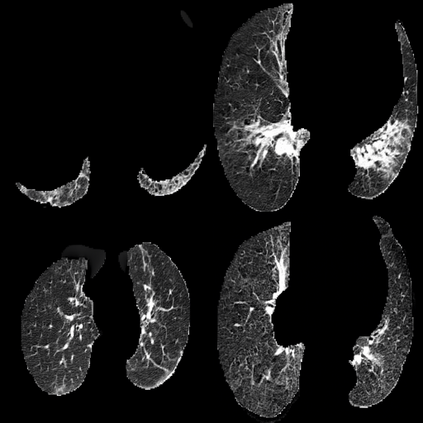

In the field of medical imaging, particularly in tasks related to early disease detection and prognosis, understanding the reasoning behind AI model predictions is imperative for assessing their reliability. Conventional explanation methods encounter challenges in identifying decisive features in medical image classifications, especially when discriminative features are subtle or not immediately evident. To address this limitation, we propose an agent model capable of generating counterfactual images that prompt different decisions when plugged into a black box model. By employing this agent model, we can uncover influential image patterns that impact the black model's final predictions. Through our methodology, we efficiently identify features that influence decisions of the deep black box. We validated our approach in the rigorous domain of medical prognosis tasks, showcasing its efficacy and potential to enhance the reliability of deep learning models in medical image classification compared to existing interpretation methods. The code will be publicly available at https://github.com/ayanglab/DiffExplainer.